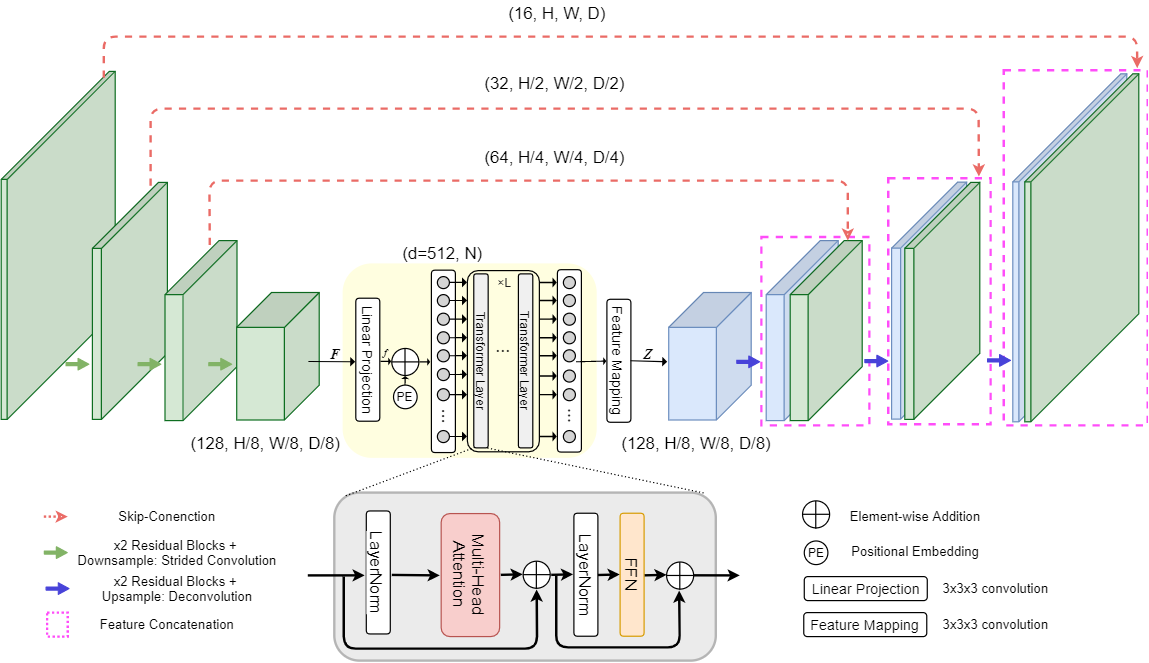

Our custom modifications (see Figure1 and Figure2 for comparison with original TransBTS):

-

•

We add Squeeze-and-Excitation blocks [5] to every layer of an encoder. SE blocks help perform dynamic channel-wise feature recalibration.

-

•

The depth of the model was increased compared to TransBTS by adding one layer in encoder and correspondingly in decoder.

-

•

We also replaced positional encoding from TransBTS with a learnable MLP block, for more details please refer to Section 2.4.